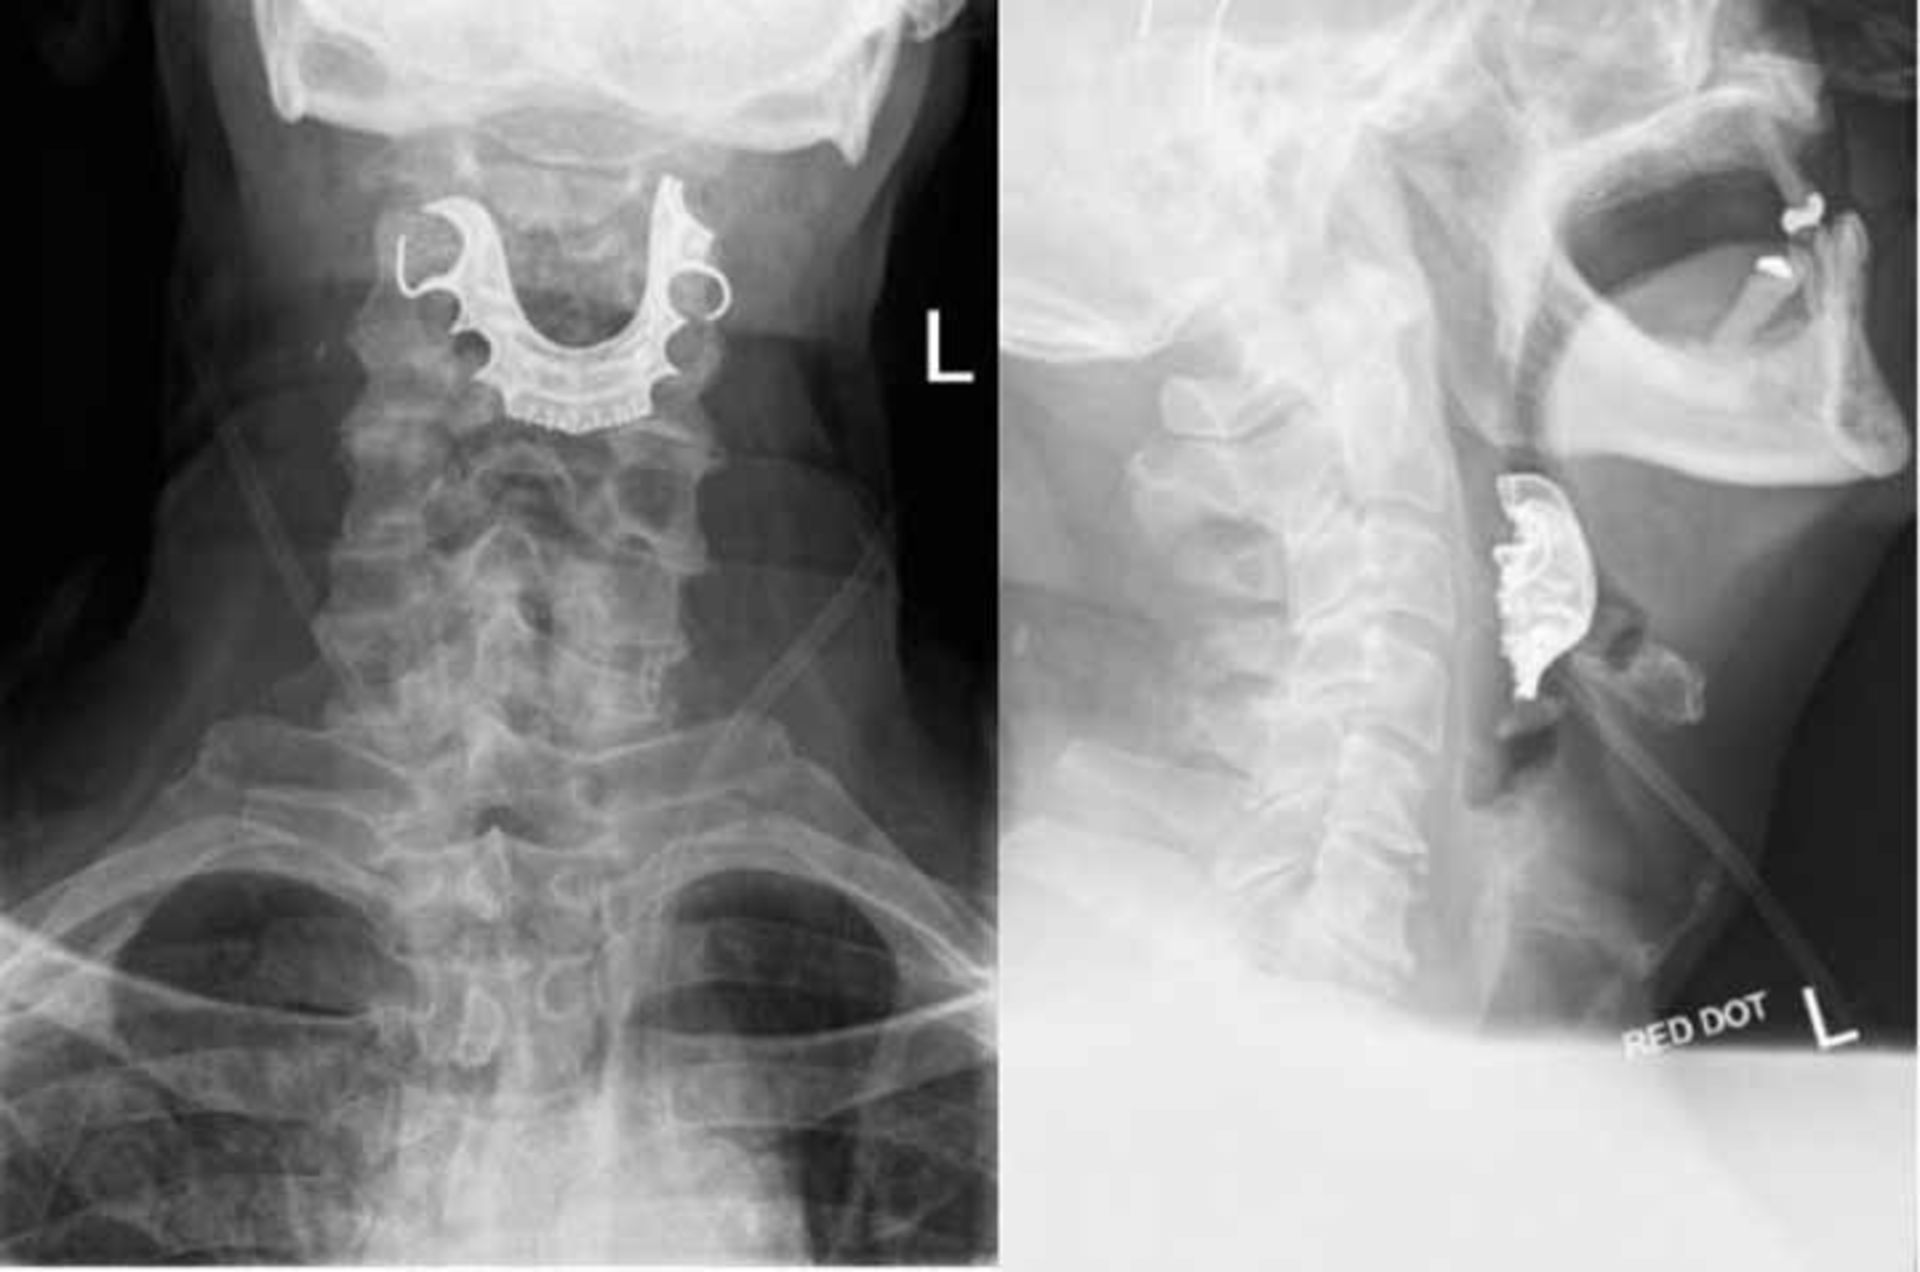

یک مرد مسن که پس از یک عمل جراحی معمولی برای یک هفته دچار خونریزی و درد شدید در گلویش شده بود به پزشکان مراجعه کرد و پزشکان با عکس‌برداری متوجه شیء عجیبی در گلوی او شدند! پزشکان اعلام کردند، بیمار مسن آن‌ها هفته‌ای کابوس‌وار را با سهل‌انگاری متخصصان اتاق عمل سپری کرده و مجبور شده، چند هفته هم در بیمارستان بستری شود تا عمل‌ جراحی دیگری را هم انجام دهد.

براساس گزارش نشریه «پزشکی بی‌ام‌جی(BMJ)»، دردها و خونریزی این مرد ۷۲ ساله انگلستانی بلافاصله پس از عمل جراحی موفق خارج کردن توده‌ای خوش‌خیم از سینه‌اش شروع شدند. دهان این بیمار دائما خون‌‌ریزی می‌کرد و او در بلع غذا هم مشکل داشت. بیمار پس از ۶ روز به اورژانس مراجعه کرد. پزشکان در ابتدا مشکوک بودند که علائم وی نتیجه عفونت دستگاه تنفسی و همچنین عوارض جانبی لوله‌گذاری در حین عمل است. بدین‌ترتیب، پزشکان بیمار بیچاره را با چند آنتی‌بیوتیک و داروهای دیگر به خانه فرستادند. بااین‌حال، او دو روز دیگر با حال بدتری به اورژانس مراجعه کرد و گفت که حتی نمی‌تواند داروهایی را که به او داده‌اند مصرف کند.

این بار این بیمار مسن در بیمارستان بستری شد، اگرچه پزشکان هنوز به اشتباه تصور می‌کردند که بیمار آن‌ها، به ذات‌الریه شدید مبتلا شده است. اما خوشبختانه پزشکان دیگری به پرونده این بیمار علاقه‌مند شدند و او را معاینه کردند و پس از عکس‌برداری‌ها مشخص شد که شیء عجیبی راه گلوی بیمار را مسدود کرده است. و همین‌جا بود که مرد مسن فاش کرد که دندان‌های مصنوعیش حدود یک هفته است که به‌طرز مشکوکی گم شدند. این اولین باری نیست که پزشکان به‌طور اتفاقی باعث شدند که بیماران در طی یک عمل جراحی یا در حین انجام بیهوشی، دندان‌های مصنوعی خود را ببلعند. به گزارش همین نشریه، طی یک دوره ۱۵ ساله، ۸۳ مورد از این دست گزارش شده از جمله موردی که منجر به مرگ بیمار شده است.